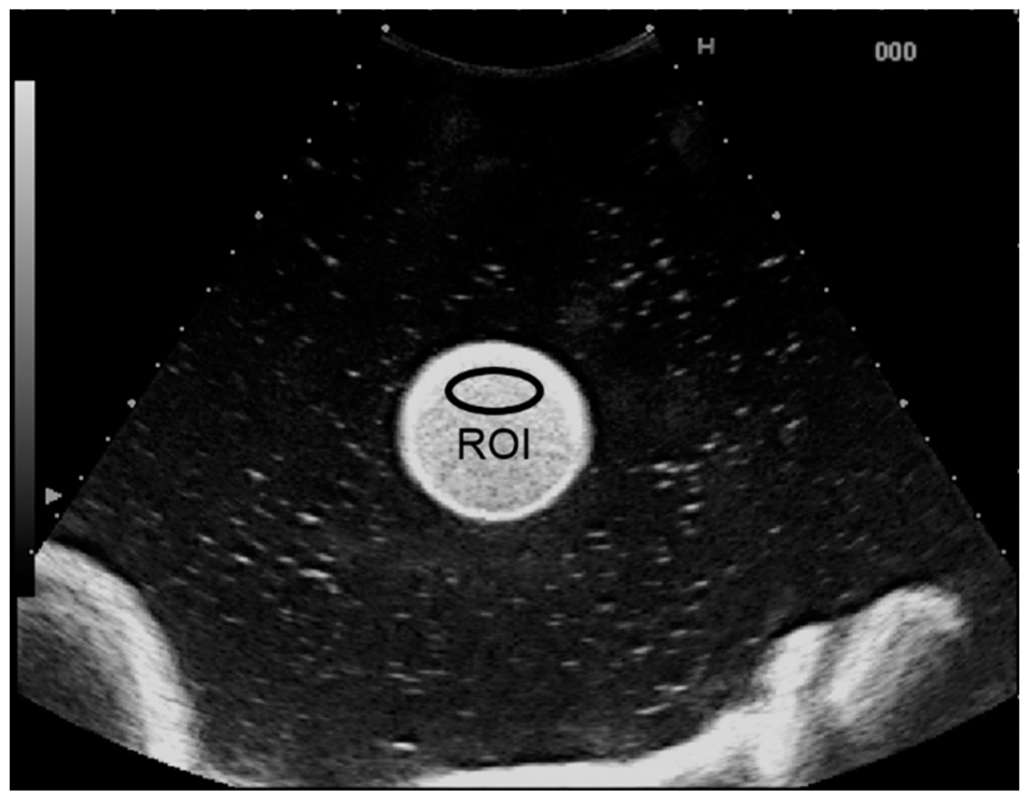

Microbubble solutions of the perflubutane contrast agent (Sonazoid; Daiichi-Sankyo, Tokyo, Japan) were prepared by mixing with purified water to final concentrations of 1.91, 3.81, 15.3, 61.0, and 244.1 μL/L. These solutions were each enclosed in a cylindrical rubber bag (diameter, 35 mm; height, 180 mm; thickness, 0.03 mm) that was attached near the center of a tank filled with purified water (Figure 1). A transducer was placed on the upper surface of the filled rubber bag. Ultrasound images of each solution were recorded for 10 s using an ultrasound system (HV900; Hitachi Medical Corporation, Tokyo, Japan) fitted with a 3.5-MHz convex-array transducer (EUP-C715) with a mechanical index of 0.17. Image analysis was performed using a brightness measurement program installed on the ultrasound system. An ellipsoidal region of interest (ROI) was placed within the solution (Figure 2), and CI in dB units was determined from the received signal using the equation 10 × log10CI. The contrast agent concentration was also calculated in dB as 10 × log10[C/C0], where C was the contrast agent concentration in each solution and C0 was the reference value of 1.91 μL/L. A linear regression analysis was used to examine the relationship between CIdB and the concentration.

Figure 2.

Ultrasound image of the contrast agent solution. The contrast signal intensity (CI) was measured in the region of interest (ROI) placed within the solution.